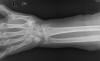

Fractura de radio.

Fractura de radio tras caída casual.